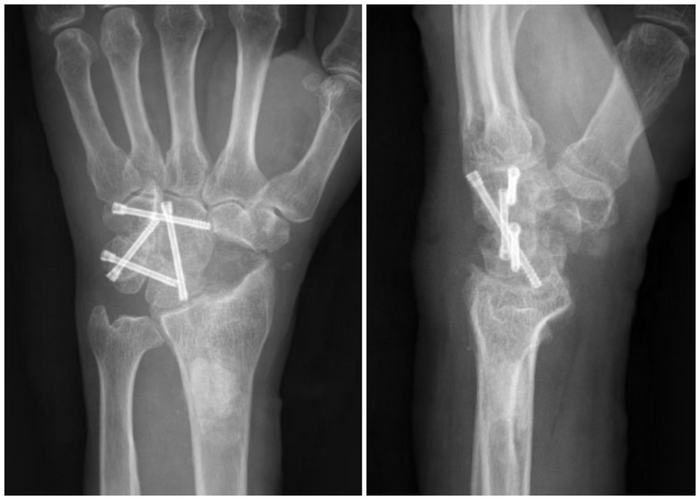

日前,烟台山医院手外一科完成了烟台市首例腕关节镜下四角融合术,为一位饱受腕关节疾病困扰的 58 岁患者带去了希望。该手术由社烟台市委会常委、主任医师付胜强领衔,李晓副主任医师、徐俊涛主治医师共同参与,这标志着烟台山医院在手外科微创手术领域取得了新突破,达到了业内先进水平。

患者的困境与求医之路 该患者是一位农民,靠双手养家糊口。然而,命运却跟他开了个残酷的玩笑,腕关节的疼痛逐渐成为他生活与劳作的巨大阻碍。起初,腕部的不适只是偶尔闪现,他并未太过在意,以为只是劳作后的疲劳反应,简单休息后便又继续田间的忙碌。但随着时间推移,疼痛愈发频繁且剧烈,不仅影响到他日常的农活,连简单的抬手、握拳动作都变得异常艰难,夜晚更是常常被腕部的刺痛惊醒。 在家人的劝说下,他踏上了求医之路。辗转多家医院后,经X线片和MRI检查,最终被确诊为舟月分离导致的SLAC腕四期病变。这一病症使得桡舟关节、头月关节、钩头关节均出现严重关节炎,软骨剥脱,软骨下骨外露,腕关节的正常结构与功能遭受极大破坏,若不及时治疗,手部功能将进一步恶化,甚至可能面临残疾的风险。 传统切开手术存有局限 面对如此复杂棘手的病症,传统的切开手术曾是主要治疗手段之一。传统切开手术需要在腕关节处切开较大的切口,以充分暴露病变部位,这就如同对腕关节进行了一场“大刀阔斧”的拆解。一方面,大面积的切口意味着要切断诸多周围的软组织、韧带等结构,术后极易引发局部粘连,严重影响关节活动度,让患者在术后康复过程中面临漫长而艰难的功能锻炼阶段,且效果往往不尽如人意。另一方面,切开手术创伤大、出血多,术中视野相对有限,对于一些细微病变的处理难以做到精准到位,就好比在昏暗灯光下进行精细的雕刻工作,容易遗漏一些隐藏较深的病灶,增加了手术风险与术后复发的可能性。 腕关节镜下 四角融合术优势尽显 烟台山医院付胜强主任团队深知传统手术的弊端,在经过严谨的病例讨论与术前评估后,决定为患者实施腕关节镜下四角融合术。 手术当日,在精心的术前准备后,患者被推进手术室。与传统手术大开大合的场面截然不同,腕关节镜手术仅通过几个微小的切口,便将纤细的关节镜及手术器械探入腕关节内部。关节镜宛如医生的“第三只眼”,将腕关节内的病变情况清晰地呈现在屏幕上,细微之处纤毫毕现,为手术提供了精准的“导航”。 术中,付胜强主任熟练地操作关节镜,使用精细磨头、髓核钳等特制工具,透过微小切口直达病灶。在清除病变的舟骨时,犹如在狭窄的管道内进行一场精细的微雕手术,精准地去除病变组织,最大限度保留了健康的骨与软组织,将手术创伤降到最低。随后,对各个病变关节面的处理更是有条不紊,依次暴露并清除头月、钩头、月三角、钩三角各关节对应软骨面,操作精准度远超传统手术。 克氏针固定各关节环节,如同搭建稳固的“脚手架”,为后续置入3.0 空心加压螺钉奠定坚实基础。每一步操作都在关节镜的实时监控下进行,术中拍片再次确认固定位置良好,确保每一枚螺钉都精准就位,为腕关节的融合与康复提供可靠保障。 相较于传统切开手术,此次腕关节镜下四角融合术优势显著: 从创伤层面看,微小切口极大减少了对周围组织的破坏,术后切口愈合快,疤痕微小,几乎不影响腕部外观。周围软组织、韧带等结构得以完整保留,有效避免了术后粘连的发生,为患者术后快速康复、恢复手部功能创造了有利条件。 出血少是另一大突出优势,术中几乎看不到大量出血的场景,这不仅降低了因失血过多引发的各类风险,也减少了术后输血的可能性,减轻了患者身体负担,让患者在术后能以更快的速度恢复体力,投入到后续康复训练中。 精准度更是腕关节镜手术的“王牌”。凭借高清的关节镜视野,医生能够清晰辨别正常组织与病变部位,对病灶的清除做到“斩草除根”,同时避免误伤到周围重要结构,大大提高了手术治疗效果,降低了术后复发风险,让患者吃下“定心丸”。